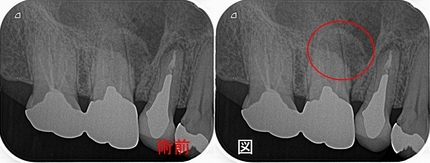

レントゲン

近心頬側根に大きな根尖病変が見られます。

レントゲンでは根尖病変は小さくなってきているように見えます。

レントゲンでは病変の大きさは半分ぐらいになってきています。

クラウンSet後、根尖病変は殆ど無くなっています。